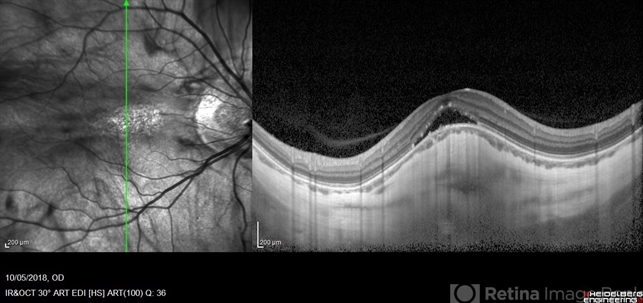

- dome shaped macula, high myopia

Optical coherence tomography system

Heidelberg Spectralis - Description

- EDI OCT of the right eye of a 17-year-old highly myopic girl. Subfoveal fluid is present. There is choroidal thinning, and scleral thickening in the foveal area.